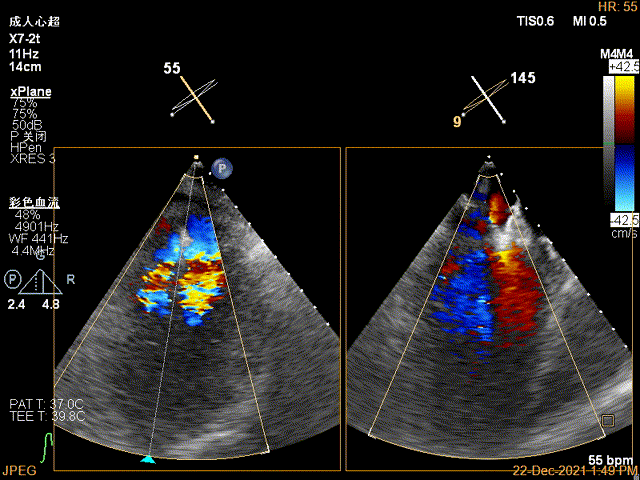

X-plane:下夹子尝试先捕获2区偏内侧瓣叶

夹子关闭过程中,Color提示2区反流逐渐减少,残余反流位于第一个夹子外侧

第一个夹子放置侯二尖瓣口平均跨瓣压差:4mmHg

肺静脉血流频谱恢复正向趋势

3D-VIEW验证前后叶抓捕情况,可观察到第一个夹子外侧的残余脱垂

3D-color-VIEW验证残余分流,位于第一个夹子外侧

肺静脉血流频谱完全恢复正向

3D-VIEW验证抓捕结果

3D-color-VIEW验证残余分流近消失